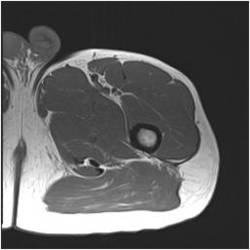

Gallery of Unlabled Radiographs from Lecture (Dr. French) - 2020

Click a thumbnail to enter the gallery display. Click the file name link at the bottom left of the gallery display to view the image at high resolution.